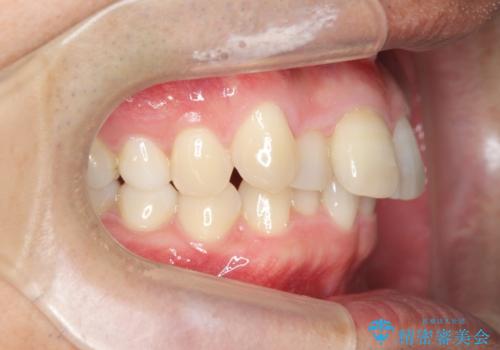

・深い噛み合わせ(ディープバイト) ・2級性の咬合関係(上顎前突)・前歯のがたつき

深い噛み合わせと上顎前突の状態を治すのに時間がかかりましたが、治療後は理想的で安定した咬合関係となりました。